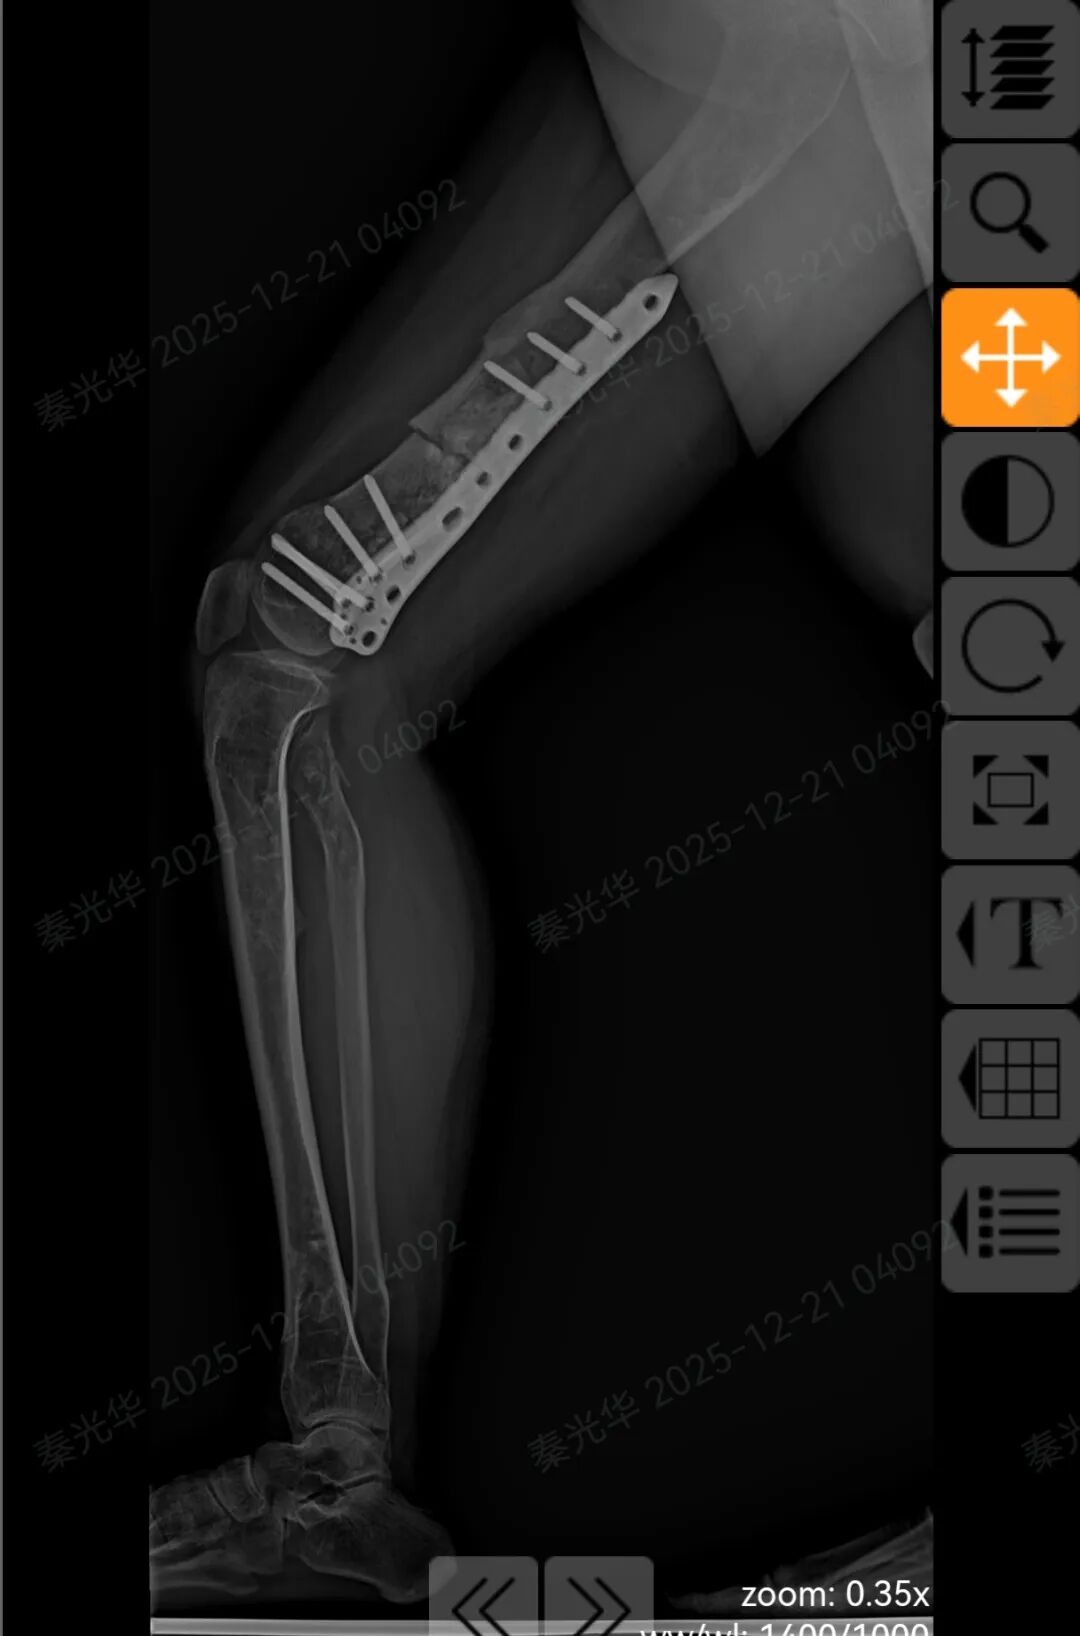

患者术后核磁显示

手术顺利完成!

术后患者右侧股骨形态恢复正常,双下肢成功等长!